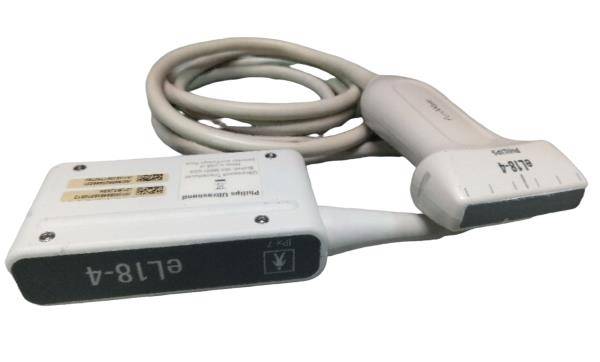

Our portable ultrasound scanner is equipped with cutting-edge technology that improves diagnostic accuracy. With its convex linear transvaginal probe, it allows for detailed imaging of internal structures. The tool is designed to be user-friendly, meaning healthcare professionals can easily operate it without extensive training. Therefore, its advanced features can help in making quick and informed decisions in clinical settings, which is essential for patient care.